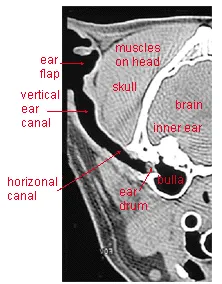

Understanding your cat’s ear structure is crucial before starting. The ear has three main parts: the outer ear, middle ear, and inner ear. Cats’ L-shaped ear canals differ from humans’, making cleaning trickier and increasing rupture risks if done improperly.

Radiograph of skull labeled.

The outer ear includes the pinna (ear flap), which funnels sound into the narrow canal bending at nearly 90 degrees. This canal leads to the eardrum separating it from the middle ear, which houses small bones, the bulla, and the eustachian tube. The inner ear links to the brain for balance and hearing.